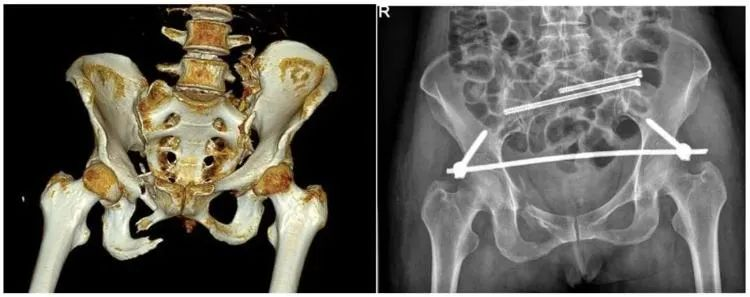

不穩(wěn)定性骨折

另外,我們根據(jù)骨盆骨折是否穩(wěn)定可以分為穩(wěn)定性的骨折和不穩(wěn)定性的骨折。如果是不穩(wěn)定性的骨折醫(yī)生可能會建議病人進行手術治療,把不穩(wěn)定性的骨折變成穩(wěn)定性的骨折。

普愛醫(yī)療推出的大平板一體式C形臂PLX119C,配置30cm×30cm平板探測器,大視野,能夠呈現(xiàn)更多圖像細節(jié),對于諸如骨盆雙側骨折類型手術或骨盆后環(huán)內固定術具有應用優(yōu)勢,一次曝光可獲取全部骨折部位影像,可簡化曝光流程,提高手術效率。